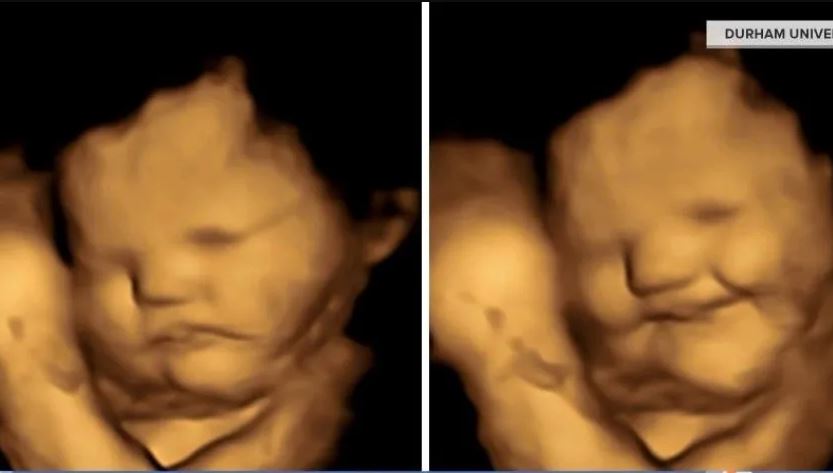

Veinte minutos después, las ecografías mostraron que la mayoría de los fetos expuestos al sabor de la col rizada parecían hacer una mueca, mientras que la mayoría de los que estuvieron expuestos a la zanahoria parecían reírse. Respecto al grupo restante, este no tuvo las mismas respuestas.

“Somos los primeros que pudimos mostrar en una ecografía las expresiones faciales en relación con los alimentos que la madre acaba de consumir”, dijo Nadja Reissland, coautora del estudio y directora de Fetal and Neonatal Research, laboratorio de la Universidad de Durham.

Las imágenes de los ultrasonidos sugieren reacciones similares a las de los niños o adultos que prueban algo amargo, dijo Reissland, pero no se sabe si los fetos realmente experimentan emociones o aversiones de manera similar.

Las muecas en los ultrasonidos “podrían ser solo los movimientos musculares que reaccionan a un sabor amargo”, dijo Reissland.